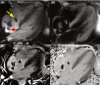

Catheter-related right atrial thrombus (CRAT) can occur in patients with sickle cell disease, particularly if additional risk factors for thrombosis are present. Cardiac MRI may differentiate thrombi from other types of atrial masses. Treatment should include anticoagulation and the timing of catheter removal should balance the potential risk of embolization.